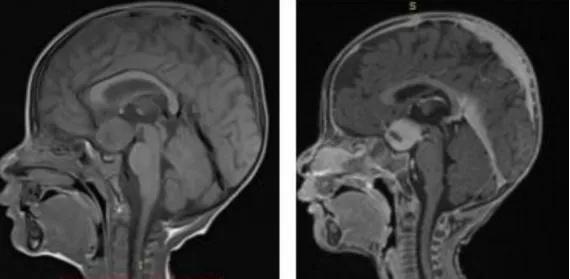

化疗的时间通常会尽可能延长,除非出现副作用(特别是听觉功能)。如果肿瘤缩小并与周围的下丘脑和视交叉结构分离,才可以讨论手术方案,特别是如果残留的肿瘤肿块是单侧时。尽管会有严重的短暂性临床上的功能紊乱,下丘脑的单侧损伤是可以耐受的。如果肿瘤弥漫性累及到整个下丘脑,预估手术尝试将是一个错误和无用的决定。

根据目前的放射学图像,肿瘤的播散仍然可疑。这种猜疑是由于在脚间池和尾部脊柱内的增强后强化的小局灶性区域引起的,但其意义应通过后期的MRI来证实。

目前,肿瘤抬高了三脑室底部,但没有影响脑脊液循环。无脑积水。